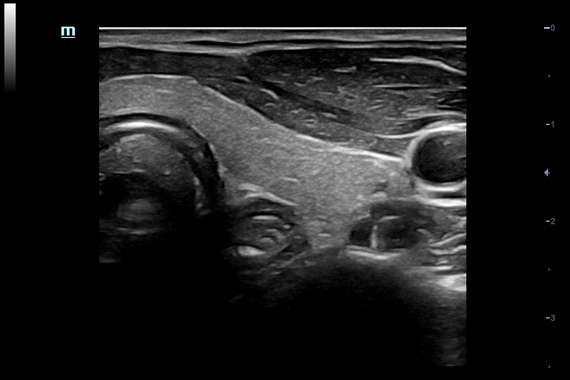

–ú–Ω–æ–≥–æ—Ñ—É–Ω–∫—Ü–∏–æ–Ω–∞–ª—å–Ω–∞—è —Å–∏—Å—Ç–µ–º–∞ DC-60 Exp —Å X-Insight –ø—Ä–µ–¥—Å—Ç–∞–≤–ª—è–µ—Ç —Å–æ–±–æ–π –∫–æ–º–ø–ª–µ–∫—Å–Ω–æ–µ —Ä–µ—à–µ–Ω–∏–µ, –∫–æ—Ç–æ—Ä–æ–µ –ø–æ–º–æ–≥–∞–µ—Ç —É–ø—Ä–∞–≤–ª—è—Ç—å –ø–æ–≤—Å–µ–¥–Ω–µ–≤–Ω–æ–π –∫–ª–∏–Ω–∏—á–µ—Å–∫–æ–π –ø—Ä–∞–∫—Ç–∏–∫–æ–π —Å –ª–µ–≥–∫–æ—Å—Ç—å—é –∏ —É–≤–µ—Ä–µ–Ω–Ω–æ—Å—Ç—å—é.

–û—Å–Ω–æ–≤—ã–≤–∞—è—Å—å –Ω–∞ –≥–ª—É–±–æ–∫–æ–º –ø–æ–Ω–∏–º–∞–Ω–∏–∏ –ø–æ—Ç—Ä–µ–±–Ω–æ—Å—Ç–µ–π –∫–ª–∏–µ–Ω—Ç–æ–≤, –∫–æ–º–ø–∞–Ω–∏—è Mindray —Ä–∞–∑—Ä–∞–±–æ—Ç–∞–ª–∞ —Å–∏—Å—Ç–µ–º—É DC-60 Exp —Å X-Insight, —á—Ç–æ–±—ã –æ–±–µ—Å–ø–µ—á–∏—Ç—å –≤—ã—Å–æ–∫—É—é –ø—Ä–æ–∏–∑–≤–æ–¥–∏—Ç–µ–ª—å–Ω–æ—Å—Ç—å –∏ —Ç–æ—á–Ω–æ—Å—Ç—å –≤–∏–∑—É–∞–ª–∏–∑–∞—Ü–∏–∏ –≤–∫—É–ø–µ —Å –Ω–∞–≥–ª—è–¥–Ω–æ—Å—Ç—å—é, –∏—Å–∫–ª—é—á–∏—Ç–µ–ª—å–Ω–æ–π –∏–Ω—Ç–µ–ª–ª–µ–∫—Ç—É–∞–ª—å–Ω–æ—Å—Ç—å—é –∏ –æ–≥—Ä–æ–º–Ω—ã–º –æ–ø—ã—Ç–æ–º.